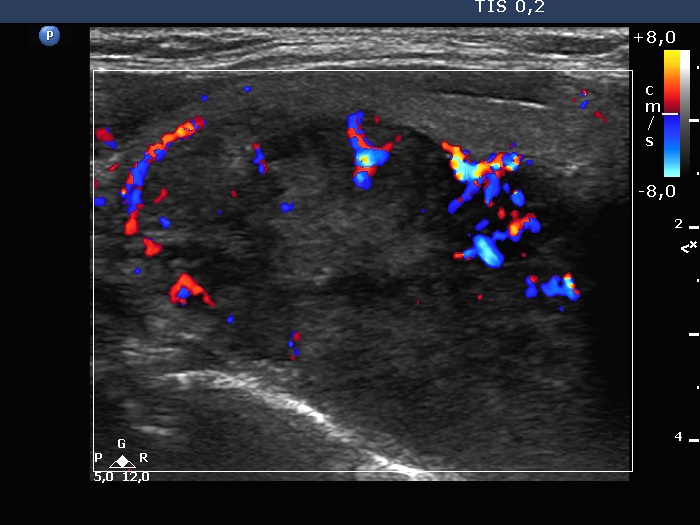

Left lobe, longitudinal scan, color Doppler mode. Both perinodular and intranodular blood flows can be detected.